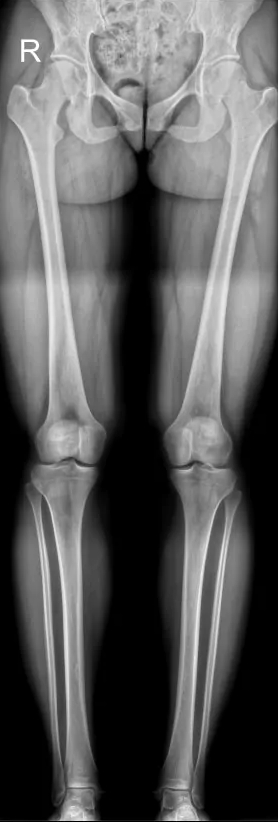

При укорочении нижней конечности,X и O-образных деформациях нижних конечностей, нужно направлять призывников на панорамную рентгенографию нижних конечностей(это современный метод, который позволяет получить единое рентгеновское изображение всей длины обеих ног, от костей таза до стоп. Для этого используются современные аппараты, которые автоматически «сшивают» серию снимков в одно цельное изображение), но такая аппаратная возможность есть не во всех мед. учреждениях.

У выше представленного призывника, при измерении истинной длины нижних конечностей, выявлено укорочение правой нижней конечности на 2.5 см., что соответствует ст.69в-В(ограниченно годен к в/сл)